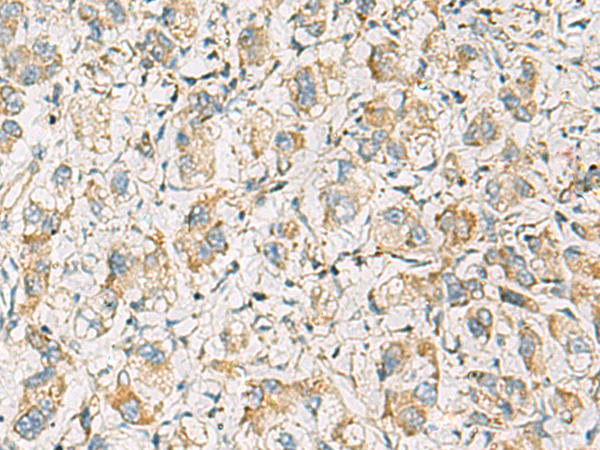

分类: 科研抗体货号: P10349别名: PTD012; PTOD012应用: WB,IHC反应种属: Human, Mouse, Rat